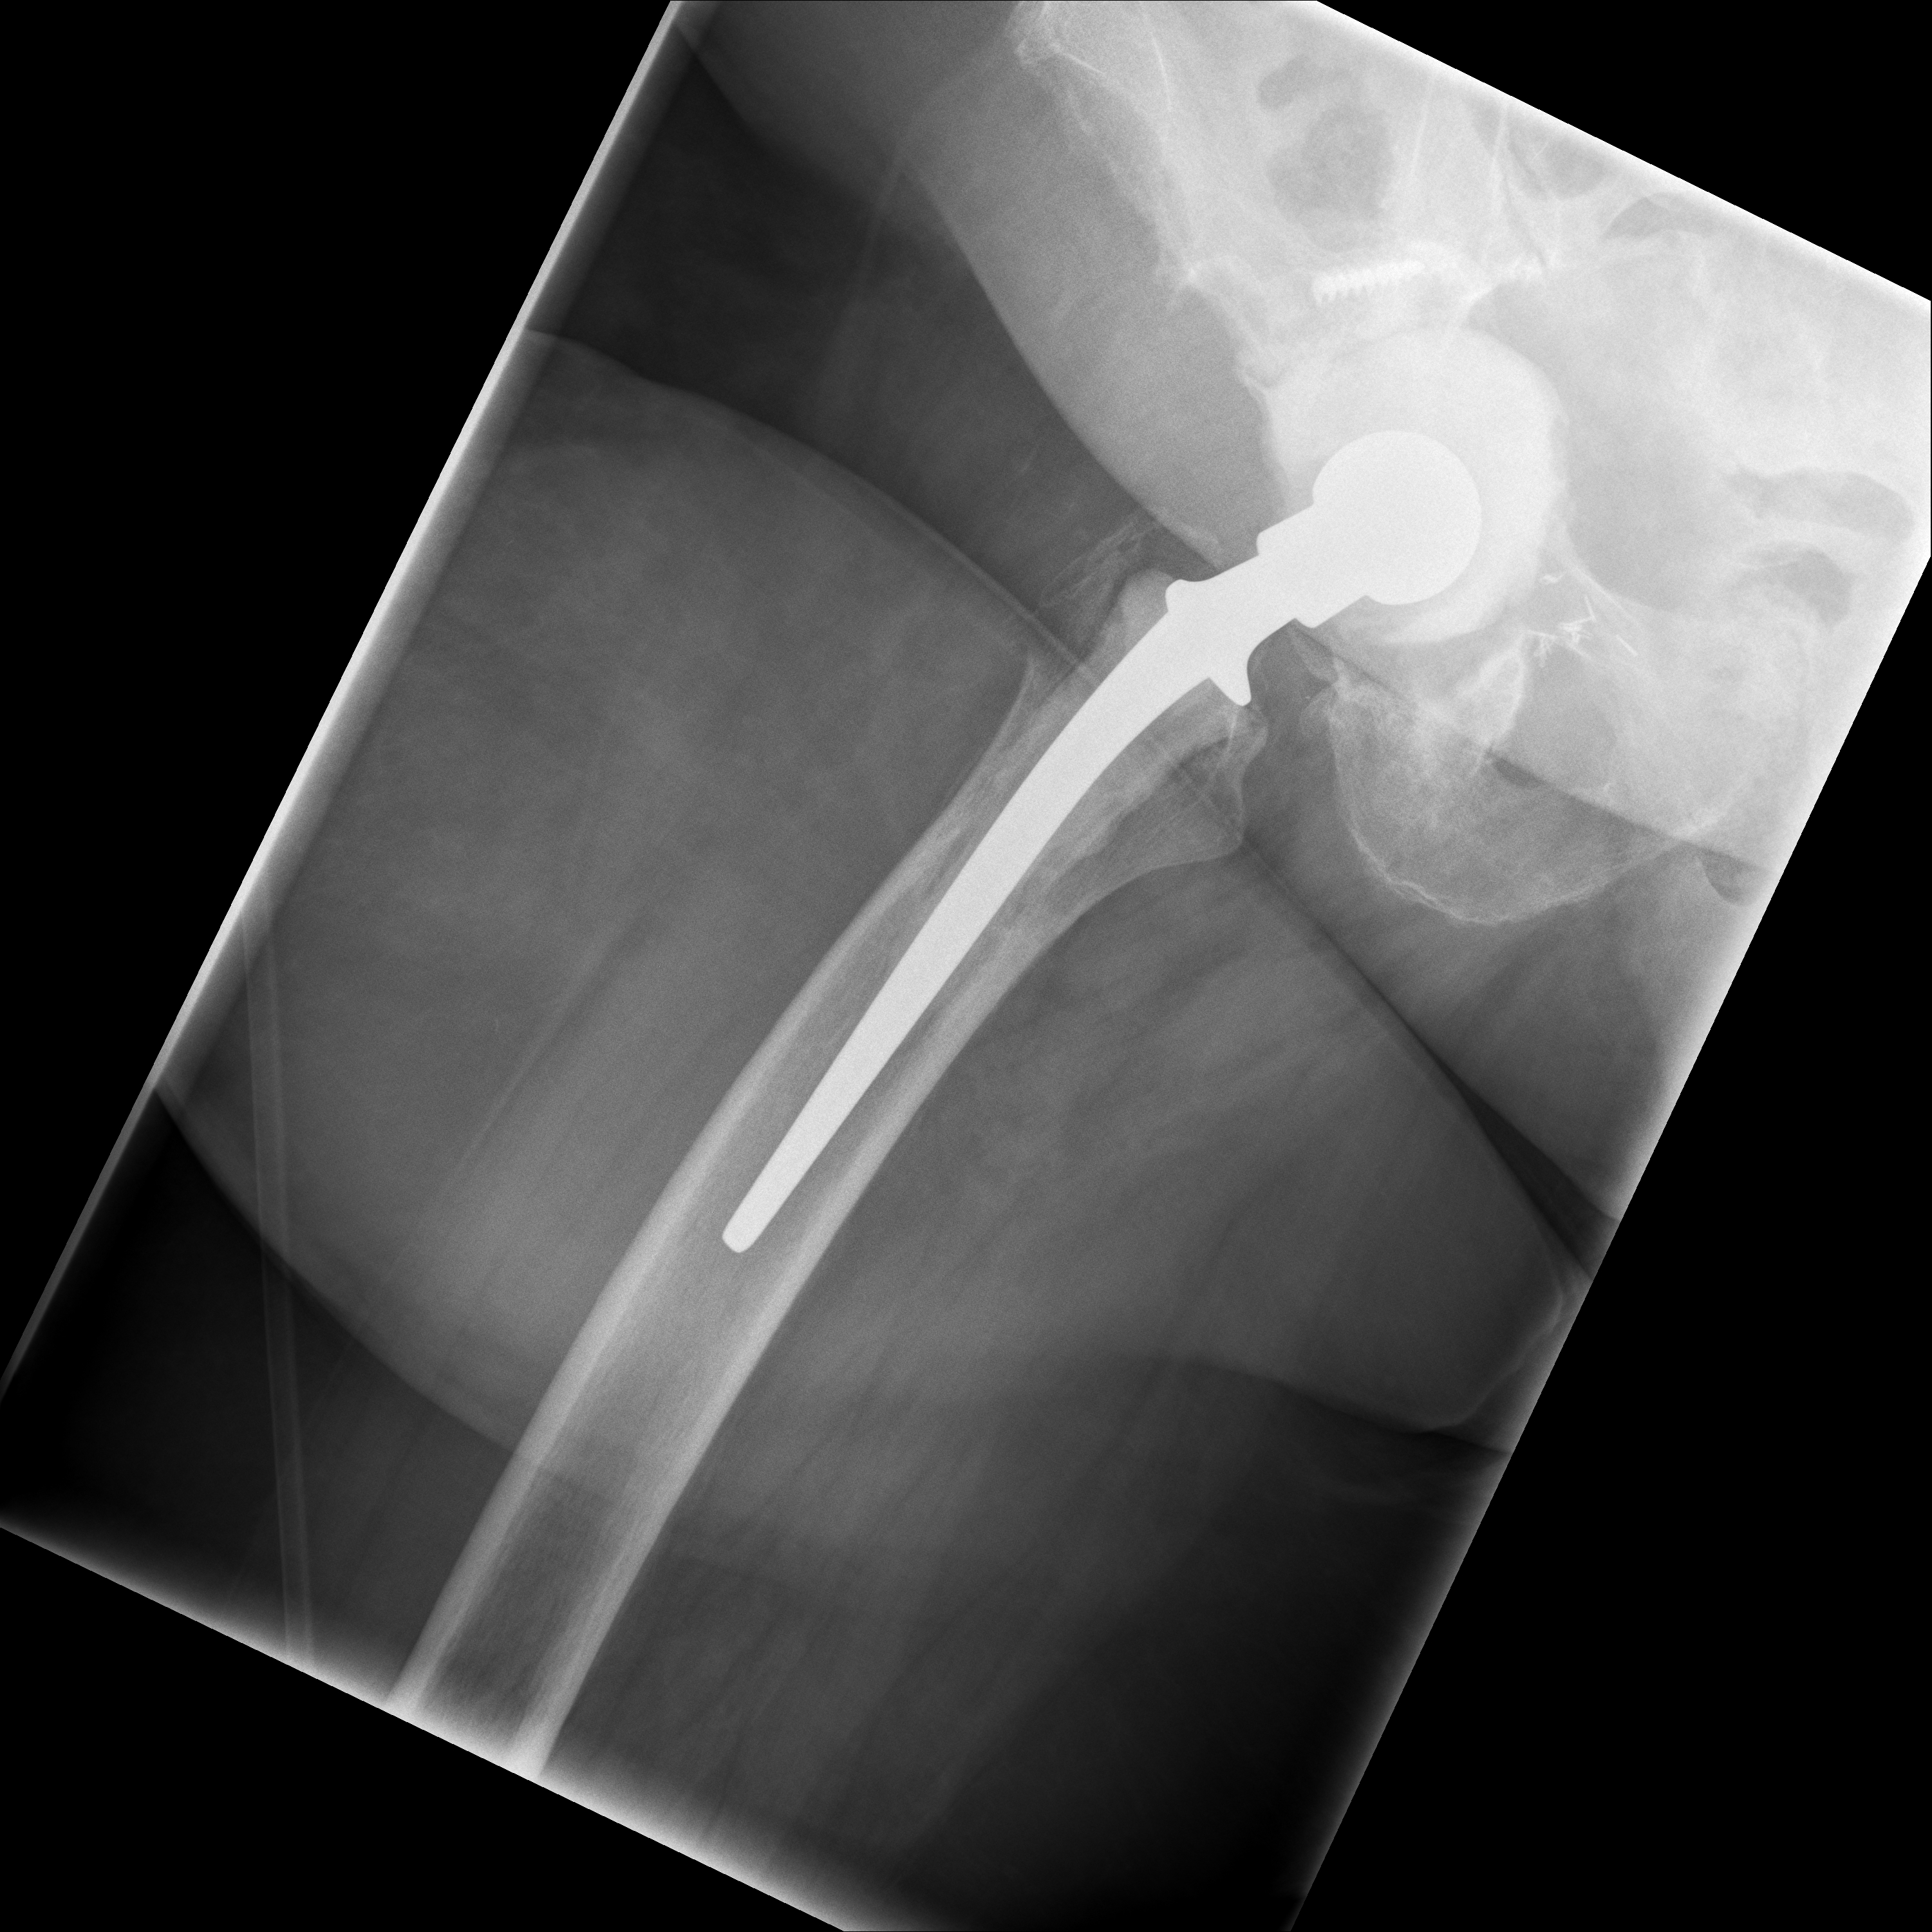

24.02.2026 - Neue TEP

Röntgen Februar 2026

Neue Hüft-TEP rechts nach Wiedereinbau

24.02.2026 - Neue TEP!

Becken 2026

24.02.2026 - Postoperativ

Röntgen Becken + Hüfte rechts (Kontrolle nach Wiedereinbau)

3 Aufnahmen | Becken tief + 2x Hüfte Lauenstein | 5 Tage nach OP

24. Februar 2026

Postoperative Röntgenkontrolle

Röntgen Becken tief + 2x Hüfte Lauenstein R – Kontrolle 5 Tage nach Wiedereinbau.

24.02.2026 - POSTOP

Röntgen Becken tief (nach Wiedereinbau)

DICOM

Kontrolle Becken 5 Tage nach Wiedereinbau TEP

Röntgen Hüfte Lauenstein R (1)

Kontrolle Hüfte 5 Tage nach Wiedereinbau TEP

Röntgen Hüfte Lauenstein R (2)